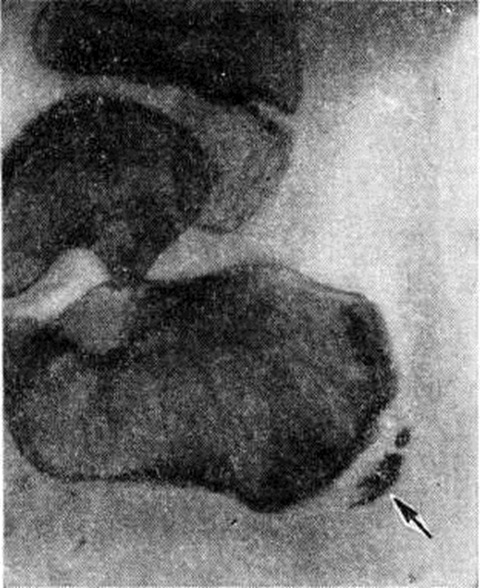

При Хаглунда — Шинда болезнь теряется гомогенность тени бугра пяточной кости, отмечается её пятнистость (секвестроподобная картина) из-за появления небольших округлых очагов резорбции с тонкими стенками и островков, состоящих из отложений минеральных солей. Возможно отделение краевых фрагментов, которые могут смещаться в сторону. Расстояние между пяточной костью и апофизом увеличивается из-за разрастания хряща (рисунок). Контуры костных поверхностей неровные. Нередко наблюдается интенсивная гомогенная минерализация бугра пяточной кости. Возможно образование на его месте двух-трёх фрагментов, не одинаковых по форме и содержанию минеральных солей.

Рис

Рентгенограмма пяточной области (боковая проекция) при болезни Хаглунда — Шинца: расстояние между пяточной костью и апофизом (указан стрелкой) увеличено; контуры апофиза неровные, в его верхней части виден отделившийся краевой фрагмент.